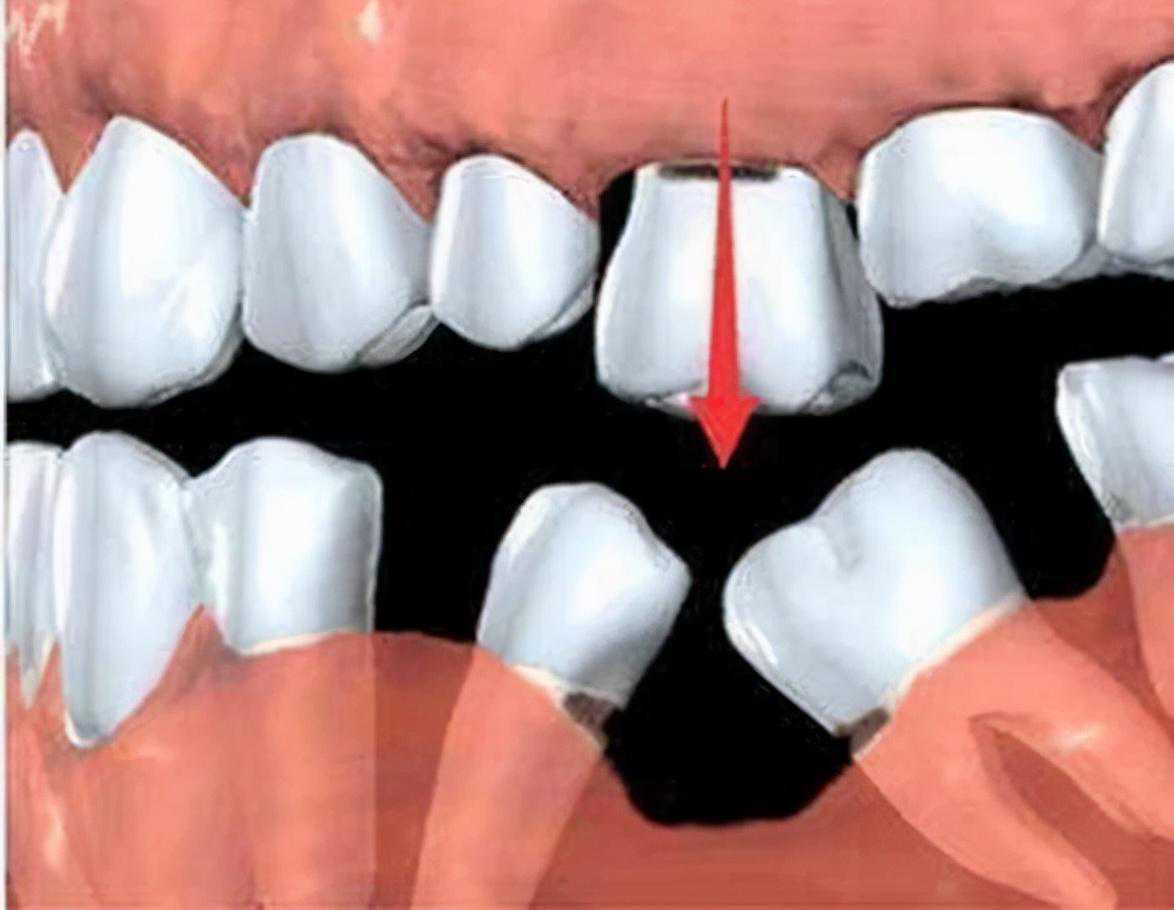

确定能手术后,才会诊断取模、制定种植牙方案。(第一次大约1个多小时)然后正式开始种植牙手术。在牙槽骨上制备一个孔,植入人工种植体。将牙骨床内严密缝合,大约一个星期后可以拆线(这次大概7--10天)。

注明:此植体只是模拟位置,不做确切种植位置。